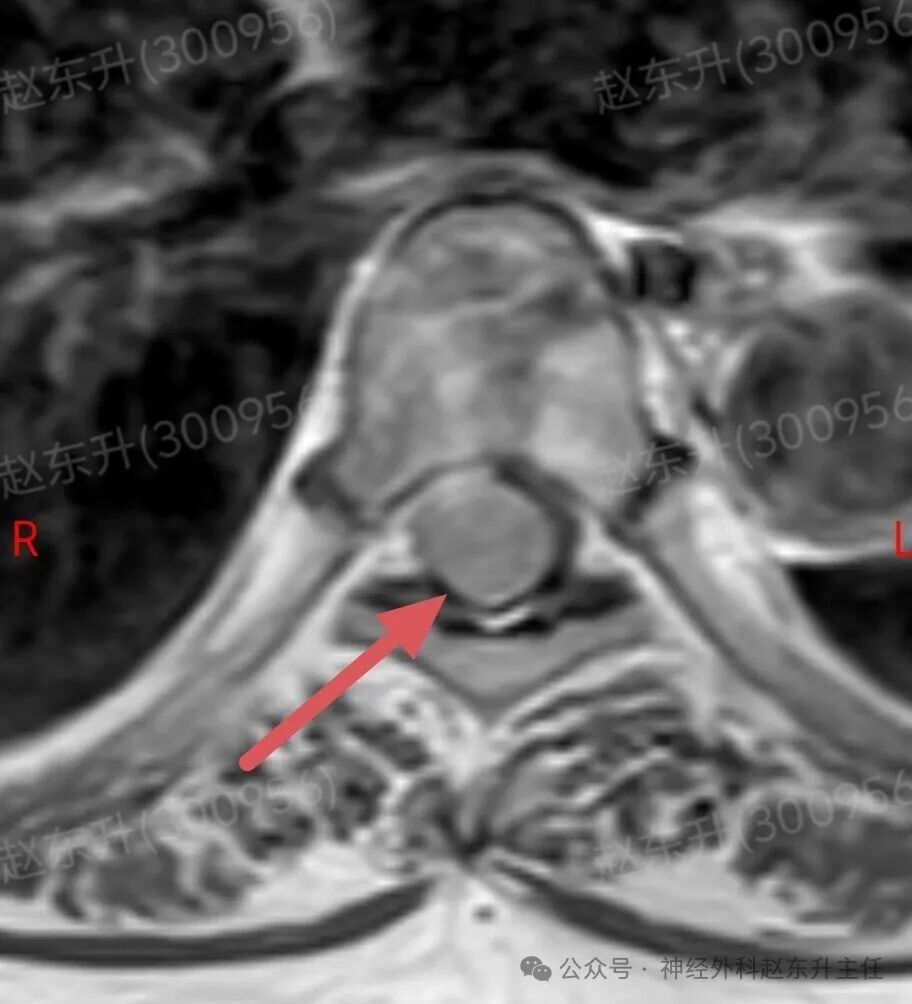

今天介绍一个58岁女性患者,因为腰部疼痛麻木伴双下肢麻木乏力半年入院的患者半年前开始出现下肢麻木乏力,但可独立行走。没有引起重视,逐渐症状加重,伴有腰部疼痛,夜间疼痛比较明显明显难以忍受,随后在当地医院查了ct和核磁共振发现椎管内一个巨大的肿瘤压迫脊髓。当地医院不敢手术,因为患者虽然疼痛麻木,疼痛评分有10分,但可以行走。随后他到西安市红会医院神经外科找到了赵东升主任,经过详细的术前评估和检查以后在全麻下显微镜下进行了肿瘤全切术后患者疼痛立即减轻,术后第2天开始做经颅磁刺激等神经康复治疗。术后一周就可以下地行走了,大小便也恢复了正常。患者感激到终于有人帮我解决了这个折磨他半年的一个疾病。

磁共振成像:是首选和确诊性检查。典型表现:T1加权像呈等或稍低信号,T2加权像呈等或稍高信号;增强扫描后呈现均匀、显著的强化,可见特征性的“硬膜尾征”(邻近硬脊膜线状强化)。